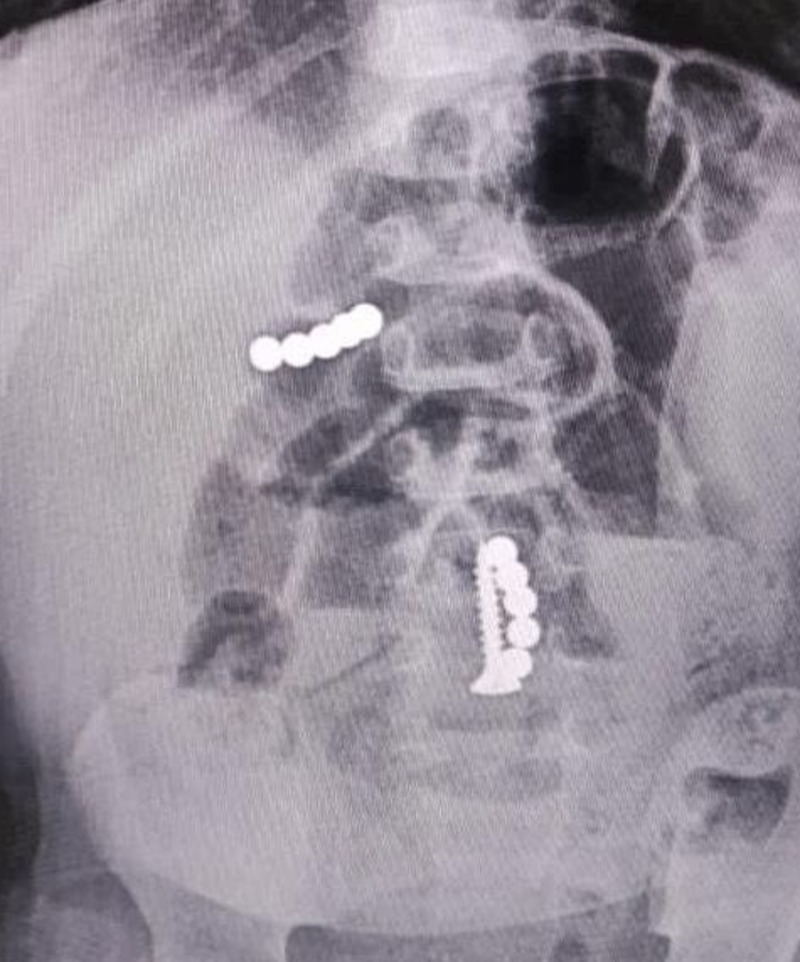

На скорой ребёнка отвезли в детскую краевую больницу. Дежурный врач, несмотря на отсутствие прямых признаков хирургического заболевания, всё же решил сделать малышу рентгенографию брюшной и грудной полости. На снимках он увидел множество магнитов и саморез в желудке и кишечнике пациента.

Хирурги провели экстренную операцию. Из тела малыша извлекли инородные тела. В месте наибольшего изменения кишечной стенки подвздошной кишки после устранения заворота произвели резекцию (частичное удаление — прим. ред). После операции ребёнок пять дней находился в реанимации. Сейчас его выписали, он чувствует себя лучше.